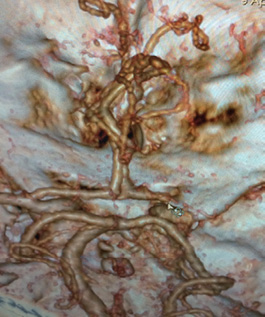

При осмотре отмечено угнетение состояния до сопора (шкала комы Глазго 9 баллов), отсутствуют движения в левых конечностях, продуктивному контакту недоступен [по шкале инсульта Национального института здоровья США (NIHSS) — 22 балла]. Выполнена стандартная рентгеновская КТ головного мозга, где выявлен очаг гиподенсной зоны (ASPECTS 8 баллов), по данным КТ-ангиографии артерий основания мозга — тромбоз М1-сегмента правой СМА. По данным ультразвукового исследования брахиоцефальных артерий — нестенозирующая стадия атеросклероза.

На полученных перфузионных картах рис. 1, 2) определяется крупная зона понижения показателей перфузии в правой височно-теменной области, что соответствует обеднению кровотока на данном уровне.

Рис. 2. Компьютерная томографическая ангиограмма головного мозга. Тромбоз правой средней мозговой артерии, сегмент М1